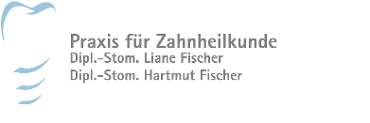

Einzelzahnlücke

Der Verlust eines einzelnen Zahnes kann jeden treffen. Oft sogar innerhalb von Sekunden: Sport gemacht, Zahn weg. Das ist zwar erschreckend, aber heute kein Drama mehr.

Implantate lösen das Problem naturnah und "unsichtbar". Zahnimplantate sind kleine, hoch entwickelte und ausgesprochen leistungsfähige Titanschrauben, die anstelle natürlicher Zahnwurzeln in den Kiefer gesetzt werden und fest in den Knochen einwachsen. Eine provisorische Versorgung kaschiert die Lücke, bis das Implantat eingeheilt ist.

Anschließend wird darauf "unsichtbar" und dauerhaft stabil Ihre neue Zahnkrone befestigt. Sie sitzt mit ihrer neuen Wurzel fest im Kiefer und ist von den natürlichen Nachbarzähnen nicht zu unterscheiden.